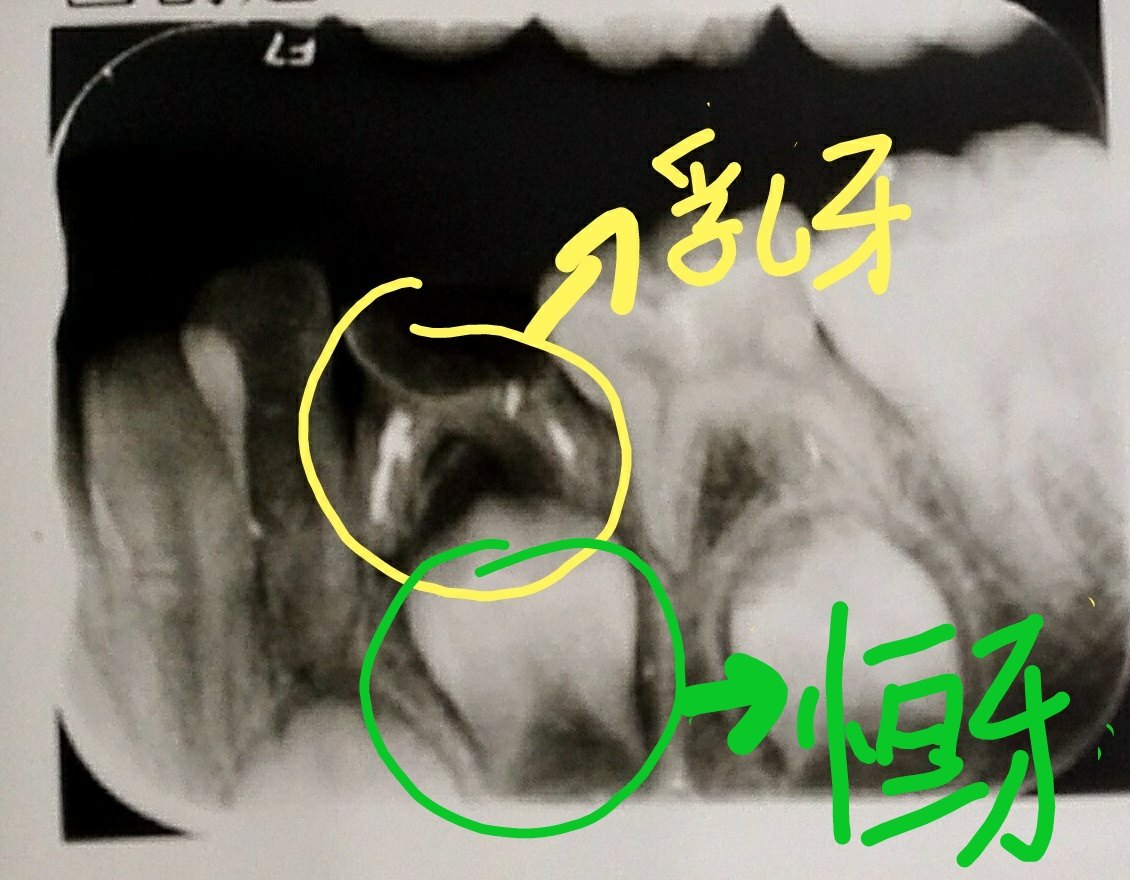

乳牙坏了影响恒牙吗?乳牙拔掉就没事了么? - 好